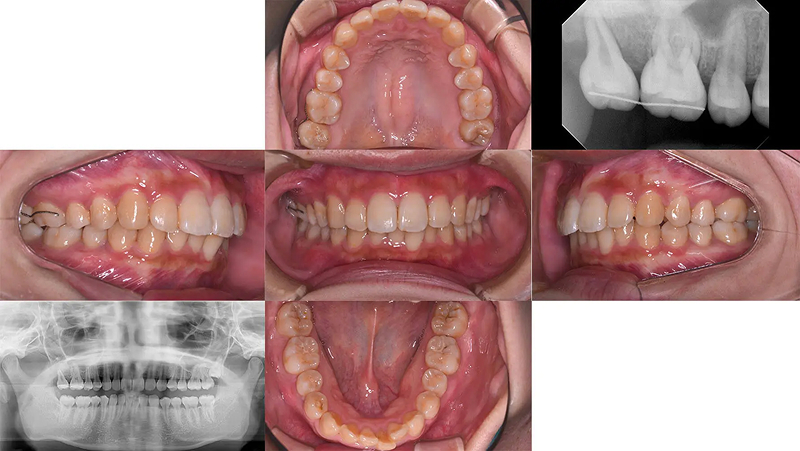

Case02マウスピース型矯正で前歯の凸凹を改善した部分矯正

前歯の凸凹が気になると受診されました。ただ、従来の矯正装置は付けたくないとのことで審美矯正を希望されました。本来なら全顎矯正の適応ですが、費用の兼ね合いもあり、前歯の凸凹だけ治療しても、審美的な改善はもちろん、機能的にも問題ないと診断しました。14枚(上下で28枚)以内のインビザライン ライトを適応しました。短期間できれいになったと大変満足していただけました。

初診 2016.5.16

矯正治療開始 2016.6.29

ファイナル 2017.1.4

| 主訴 | 前歯の凸凹を目立たない矯正で治したい |

|---|---|

| 診断 | 右側アングル1級、左側アングル3級の叢生 |

| 矯正方法 | マウスピース型矯正(インビザライン ライト) |

| 矯正期間 | 6か月・8回 |

| 費用 | 390,000円(税別) |

| 調整料 | 月1回 5,000円(税別) |